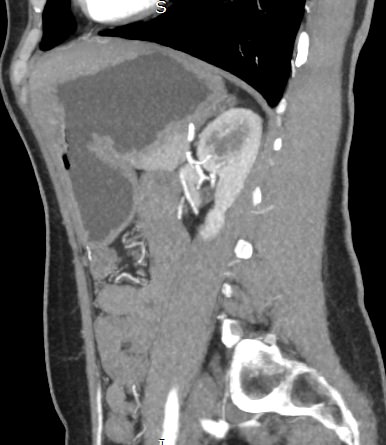

В компьютерном томографе излучатель рентгеновских лучей установлен в кольцевой части аппарата и, непрерывно вращаясь вокруг зоны исследования, производит послойное сканирование в различных плоскостях. В результате получаются снимки анатомической зоны в мельчайших подробностях, а после цифровой обработки полученных данных – точные трехмерные объемные модели исследуемой области. При этом изображения органов можно приблизить, повернуть в разные стороны, что значительно повышает точность диагностики различных заболеваний.

Для улучшения визуализации мягкотканных структур (внутренних органов, клетчаточных пространств, связок, мышц, сухожилий, кровеносных сосудов и лимфатических узлов) в ряде случаев проводится дополнительно контрастное усиление. Для этого пациенту внутривенно вводится йодсодержащий контрастный препарат, который активно поглощает рентгеновские лучи. Благодаря способности контраста накапливаться в патологических участках, они становятся хорошо видны на снимках КТ. Контрастное усиление позволяет оценить состояние сосудистой системы, выявить участки воспаления и опухолевые образования. С помощью контрастирования удается выявлять опухоли минимальных размеров, определить точные размеры и границы опухоли, степень ее воздействия на окружающие ткани.